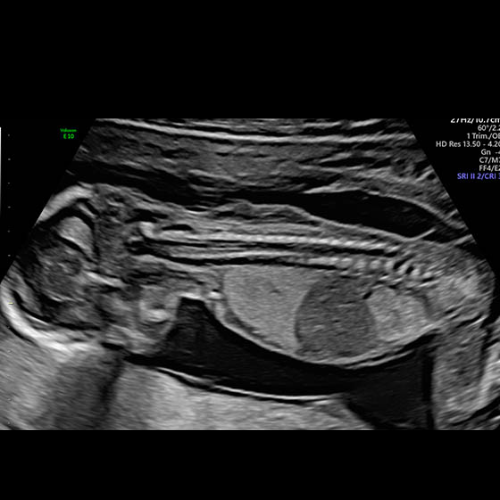

Fetal imaging

In-utero diagnostic

Over the past two decades, Dr. Alam has established an unparalleled reputation as a fetal medicine specialist and radiologist in Kolkata. His expertise encompasses first-trimester screening, fetal echocardiography, non-invasive prenatal testing (NIPT), and diagnostic fetal interventions. Across distinguished clinics—including Care IVF, Fetomat Foundation, Institute of Fetal Medicine—he has managed complex fetal conditions, from abdominal wall defects and fetal growth restriction to interpreting subtle fetal soft markers, always with a patient-centric approach and collaborative care.